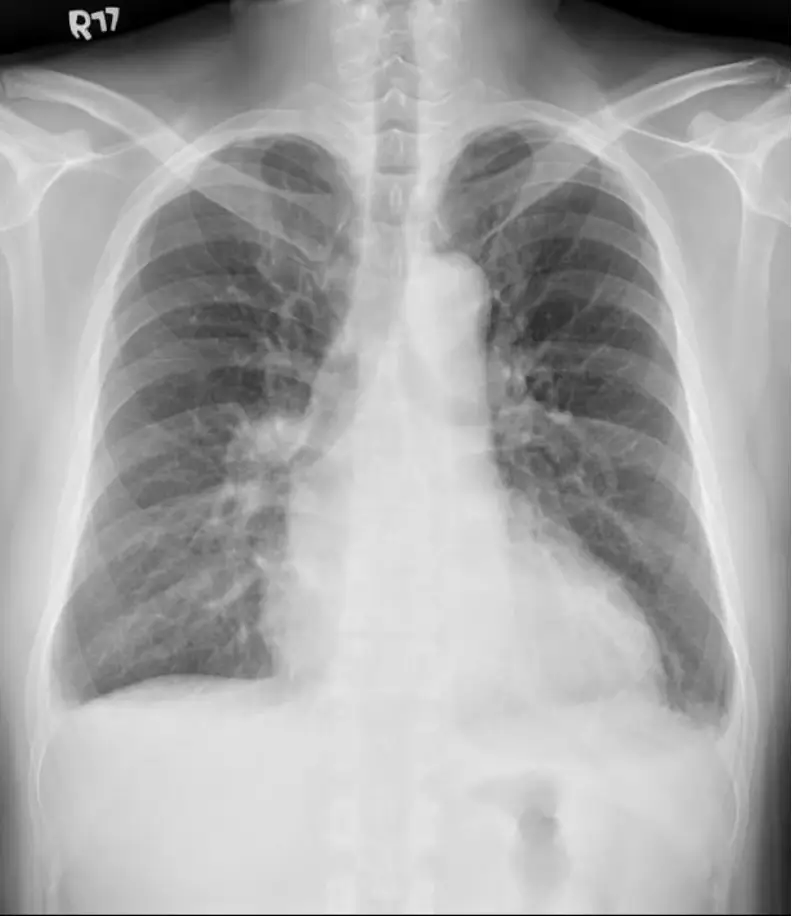

胸部 X 光可見心影顯著增大,心胸比明顯超過 0.5,顯示擴大性心肌病背景下的心臟擴大。肺野未見明顯肺水腫或肺泡浸潤,肺血管紋理不增粗,提示此刻並無急性肺水腫。